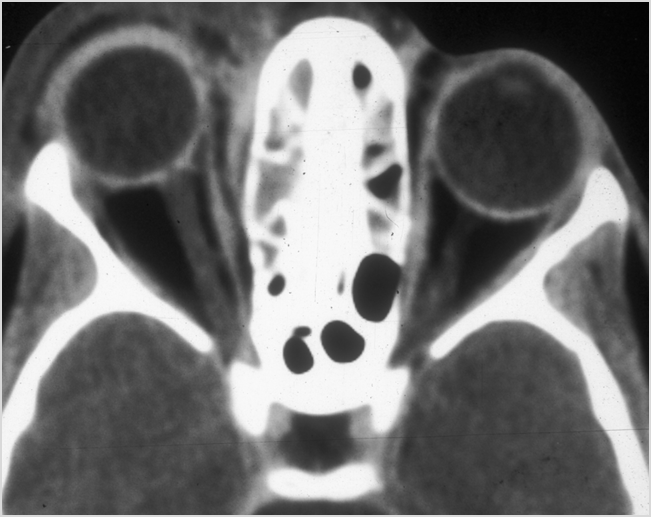

Eyes

Proptosis is present. [Yes/No]

The optic nerve is stretched in appearance. [Yes/No]

The posterior aspect of the globe is tented in appearance. [Yes/No]

The uveal scleral margin of the globe is swollen or enhancing abnormally. [Yes/No]

Signs of tension orbit or endophthalmitis are present. [Yes/No]